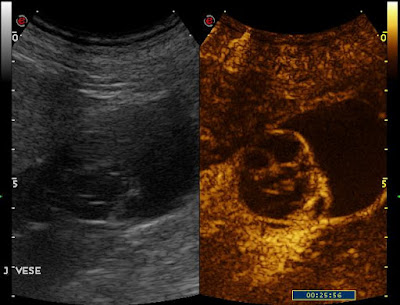

| a septumokban az ultrahangos kontrasztanyag már korai fázisban is megjelenik |

| a septumok és a cysta fala is a veseparenchymával egyező mértékben halmozzák a kontrasztanyagot |